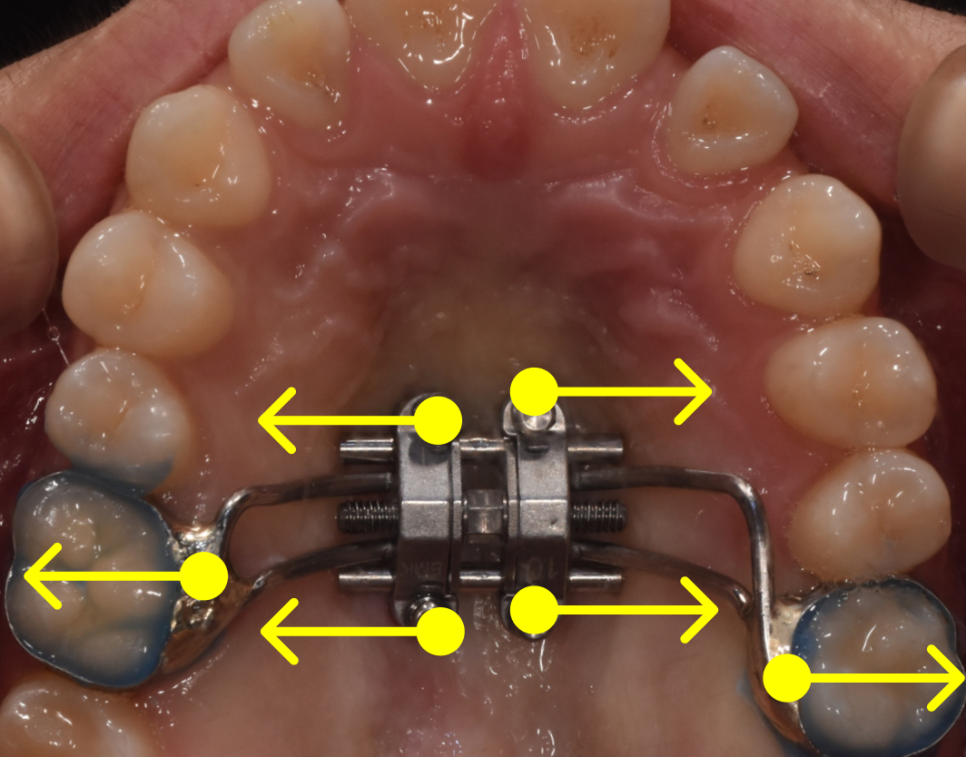

저희는 이를 위해 비교적 최근에 개발된 MARPE(Miniscrew-Assisted Rapid Palatal Expansion) 장치를 활용하기로 하였습니다.

MARPE란?

MARPE는 입천장(구개)에 미니 스크류(작은 나사)를 식립하고, 이 미니 스크류와 치아에 동시에 힘을 가하여 위턱뼈를 양옆으로 확장시키는 장치입니다.

과거에는 이러한 상악 확장 시술이 성장기 어린이들에게만 가능하다고 여겨졌습니다. 성인의 경우 입천장 뼈의 이음새(정중구개봉합)가 이미 단단하게 굳어 있어, 장치를 써도 뼈가 벌어지기보다는 치아만 바깥으로 쓰러지는 부작용이 생기기 쉬웠기 때문입니다.

하지만 미니 스크류를 활용하게 되면서 상황이 달라졌습니다. 뼈에 직접 고정된 나사가 강력하고 안정적인 지지대 역할을 해주기 때문에, 이미 성장이 끝난 성인의 단단한 뼈 이음새도 수술 없이 안전하게 벌려줄 수 있게 된 것입니다.

이 장치 덕분에 환자분은 수술대에 오르지 않고도 좁았던 위턱이라는 '근본적인 틀'을 넓힐 수 있게 되었고, 비로소 치아들이 제 자리를 찾을 수 있는 넉넉한 공간을 확보하게 되었습니다.

1단계: 상악 확장(위턱 넓히기)

가장 먼저 진행한 작업은 좁았던 위턱을 양옆으로 시원하게 넓혀주는 것이었습니다. 위턱이 확장되면서 아래턱과의 너비 균형이 맞기 시작합니다. 전후 사진을 보시면 좁았던 아치가 완만한 곡선을 그리며 넓어진 확실한 차이를 확인하실 수 있습니다.